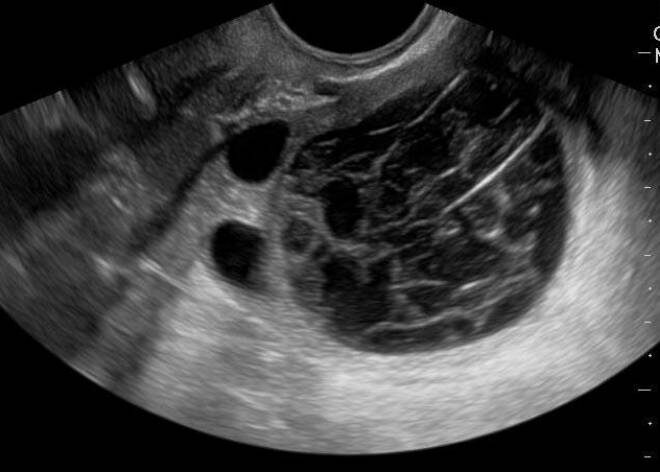

Жёлтое тело становится видимым на УЗИ при проведении его трансабдоминальным или трансвагинальным методом, особенно в период после овуляции. В это время на УЗИ видны все процессы, можно увидеть данную патологию.

При обнаружении новообразования врач кабинета ультразвукового исследования подробно рассмотрит его. Киста выглядит как полость или полости, которые заполнены жидкостью.

Киста желтого тела на УЗИ: что это значит?